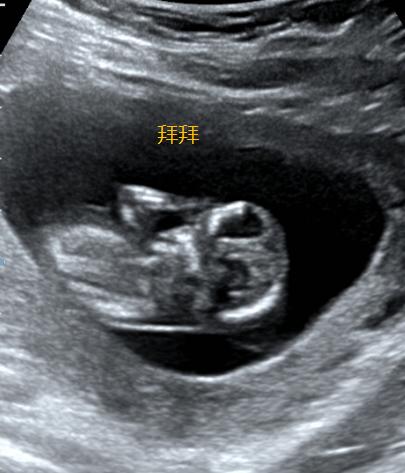

其实早在约6周的时候就可以看到宝宝有节律的心跳了。

除了心跳,我们还能看见TA的整个身体雏形了。